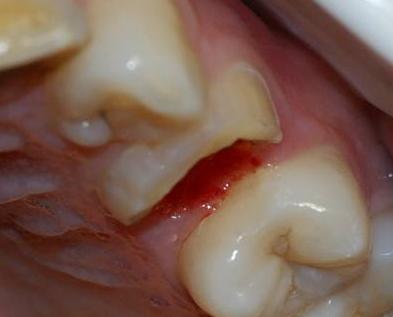

还有就是如果患者发生意外磕碰或者是外力撞击,也可能使牙齿只留下残根。这时失去的牙釉质和外部牙体的保护,髓腔和根管是暴露在空气中的,更容易感染病菌和疾病。

首先,残根是将髓腔暴露在空气中的,那么口腔内环境中复杂的菌群就很容易侵入到髓腔内部,导致牙髓炎、牙周炎等令患者出现牙齿疼痛的疾病,造成更深程度的不适。

其次,如果只留下残根的话,因其凹凸不平的表面可能会更容易残留食物残渣,如果患者没有及时进行清理的话,可能会将本来没有龋坏的牙齿变成龋齿,也有可能引发更严重的口腔问题。